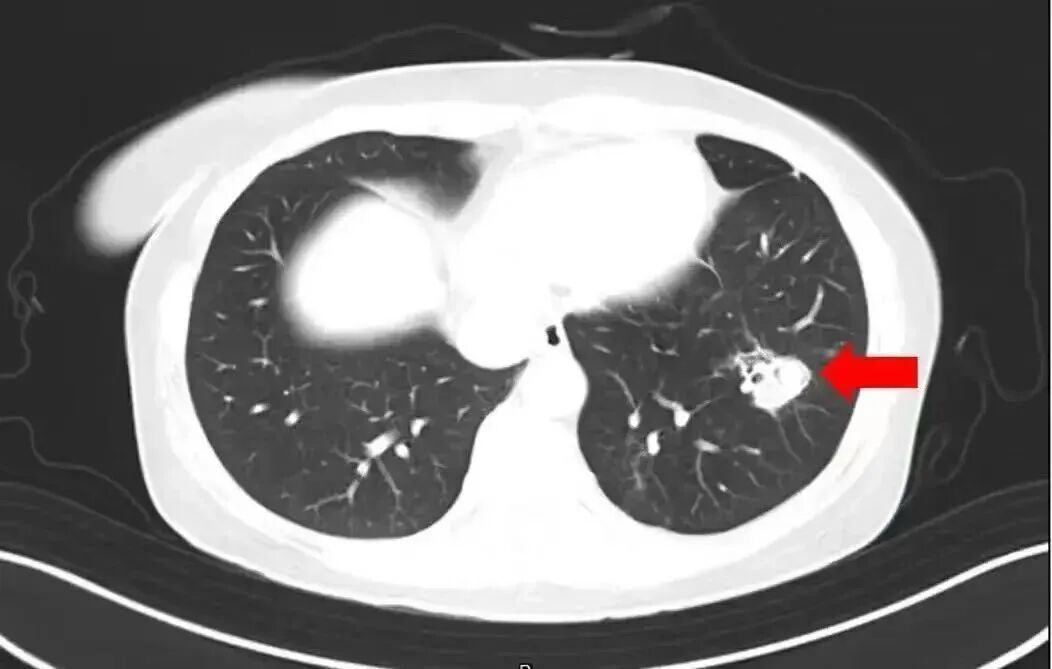

2025年1月,江苏扬州的张大爷为迎接春节开始大扫除,清扫过程中不慎吸入大量灰尘和霉菌孢子,导致哮喘发作。张大爷随即服用了常备的哮喘治疗药物,可症状反而逐渐加重。经检查,张大爷的肺部出现感染,确诊为肺曲霉病。

烟曲霉等特定霉菌,对免疫力较弱的人,还可能带来致命的肺部感染。